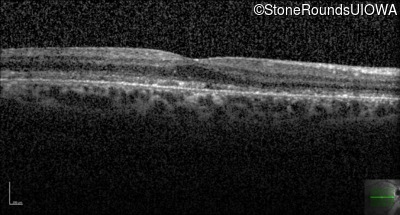

Age at visit: 56 years